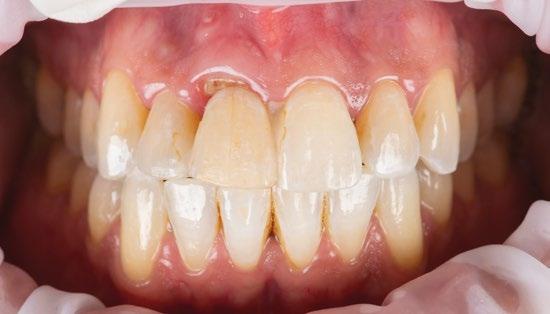

También la corona del lateral se volvió a rehacer en el año 2025 al mismo tiempo que se restauraron 23 y 24, utilizando la tecnología disponible hoy en día mediante impresión digital. (Fig. 12 a 16)

Para concluir creo que podemos afirmar que, a pesar de haber sido tratados ambos pacientes en 1987 —cuando nuestra curva de aprendizaje era aún incipiente—, estos dos casos documentan de manera inequívoca que los principios fundacionales de la implantología desarrollados por P. I. Brånemark continúan plenamente vigentes. Naturalmente, en las últimas décadas hemos sido testigos de múltiples variaciones y avances que han contribuido a perfeccionar los procedimientos y optimizar los resultados; sin embargo, la esencia permanece inalterada.

La estabilidad clínica, la integración ósea y la predictibilidad pueden mantenerse durante décadas si se seleccionan cuidadosamente los casos, se respetan los protocolos y, por supuesto, se lleva a cabo un seguimiento clínico riguroso.